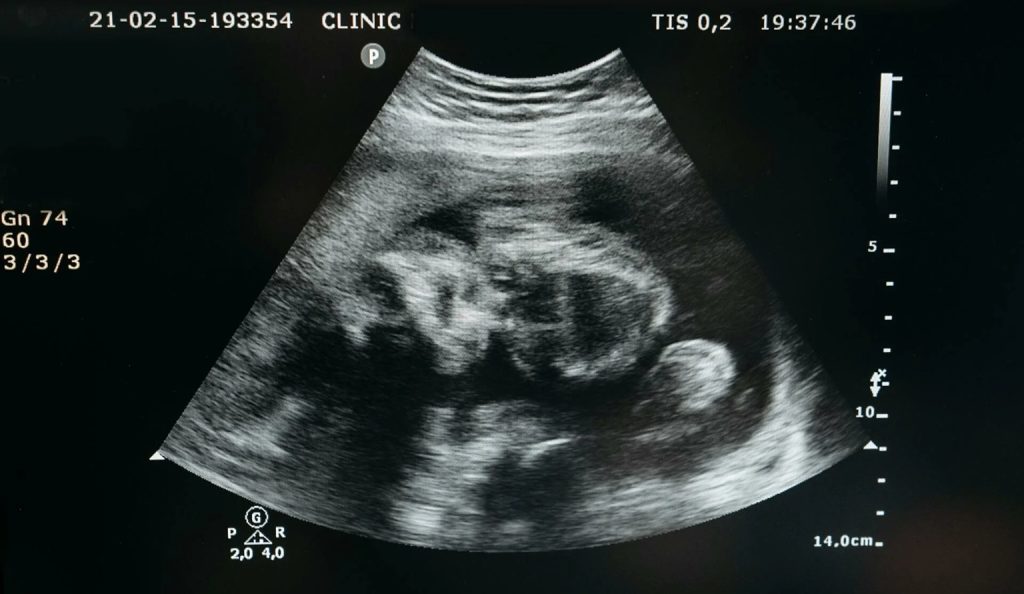

Τέσσερις μήνες μετά, η Rosie δέχεται την καθιερωμένη προγεννητική παρακολούθηση και όλα δείχνουν ότι η εγκυμοσύνη εξελίσσεται ομαλά. «Ακόμα ξυπνάω το πρωί και δεν μπορώ να πιστέψω ότι είναι αλήθεια. Δεν το πιστεύω πλήρως μέχρι να δω τις εξετάσεις και τους υπερήχους», λέει.